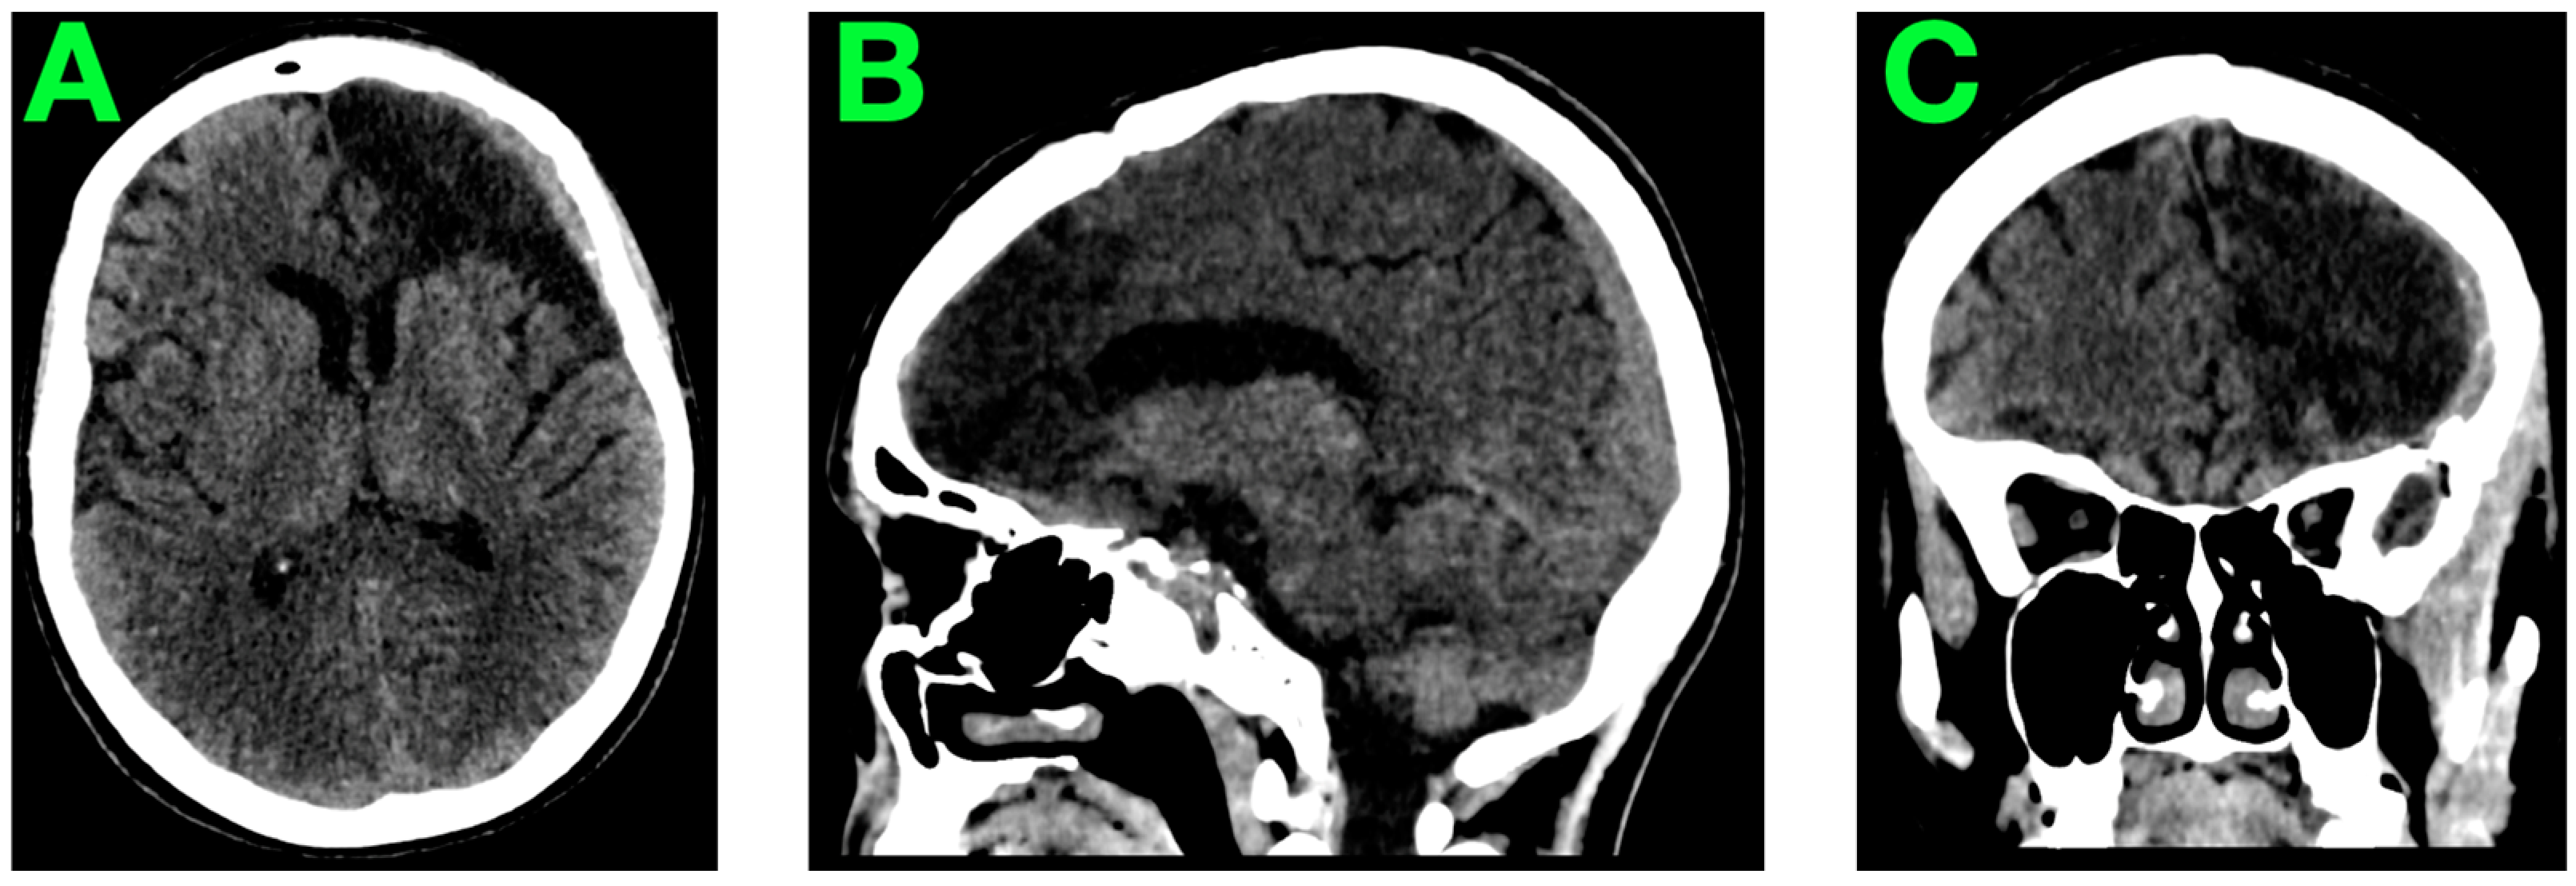

2.5. Postoperative Course

2.6. Initial Imaging and Clinical Monitoring